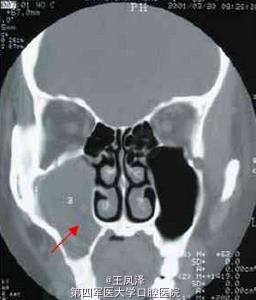

患者女性,38 岁。主诉:发现右面颊部肿物一个半月。查体:右颧弓下方2.5cm×3cm 肿物,囊性感,与周围组织无粘连。CT 鼻窦冠扫示:右上颌骨囊肿向内突入右上颌窦(齿槽骨缺损),向外突向颌骨外的软组织中。术后病理:右上颌骨囊肿,部分囊壁可见慢性炎细胞浸润。